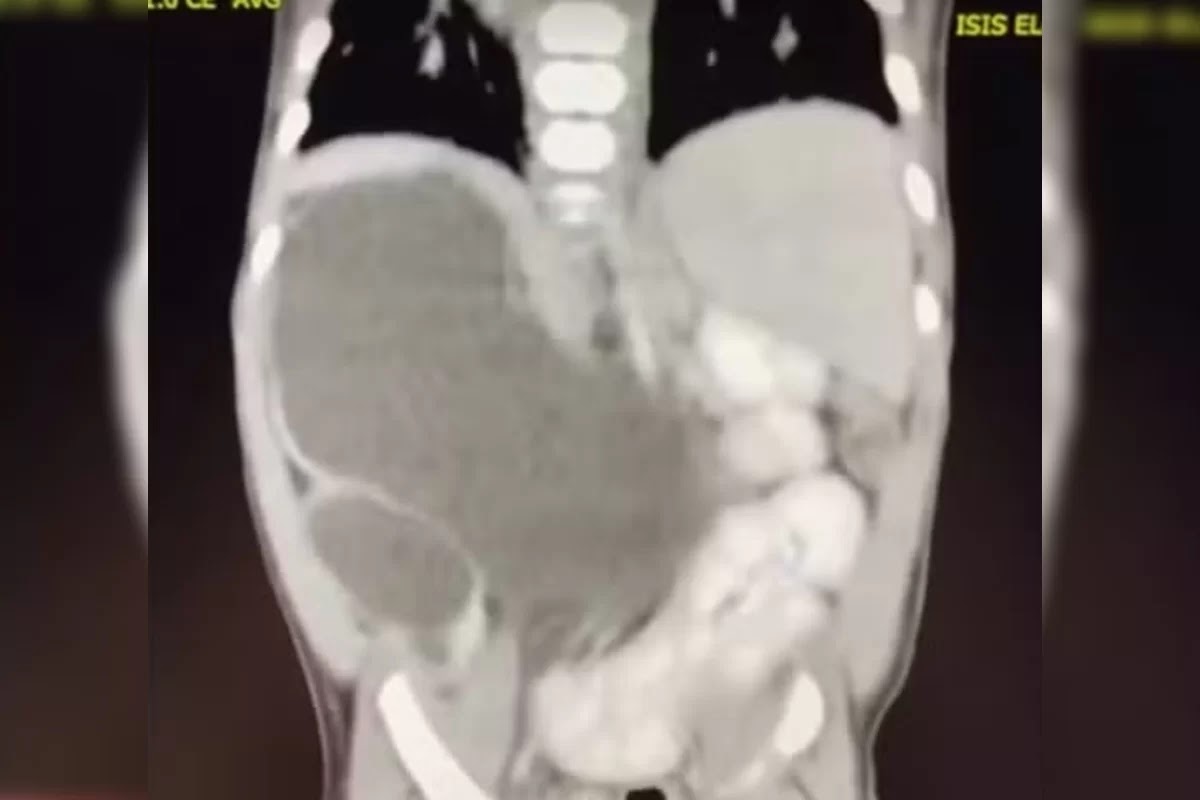

Incluída nos casos raríssimos da medicina, uma menina nasceu com quatro rins. Hoje com 1 ano e 1 mês, a pequena Isis Eloah Ferreira Alves está entre os cerca de 100 casos da medicina documentados na literatura mundial. O caso, publicado pelo G1, é é conhecido na medicina como “rins supranumerários” e demanda acompanhamento.

Aos 5 meses, quando houve a necessidade de Isis passar por uma cirurgia, os médicos confirmaram que ela tinha nascido com quatro rins. Como Formosa fica a cerca de 80 quilômetros do Distrito Federal, a menina hoje é tratada no Hospital da Criança de Brasília (HCB).